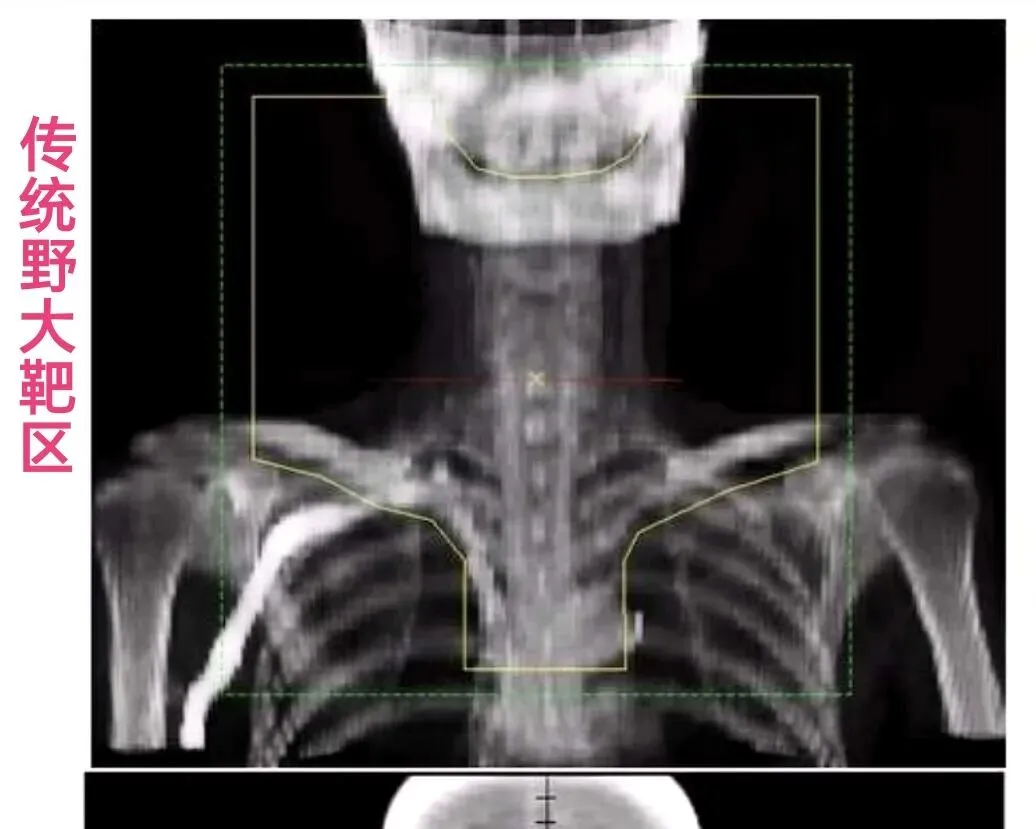

ENI(选择性淋巴结照射):

上界:颅底   下界:气管分叉

传统大野照射,覆盖广泛的淋巴引流区(如从颅底到气管分叉)。

优点是区域控制好,缺点是毒性大。